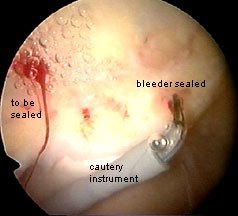

And while I am talking about problems, I just want to mention again the issue of bleeding. It is quite easy to see when you have cut a bleeder. I make sure that any bleeders are cauterised.